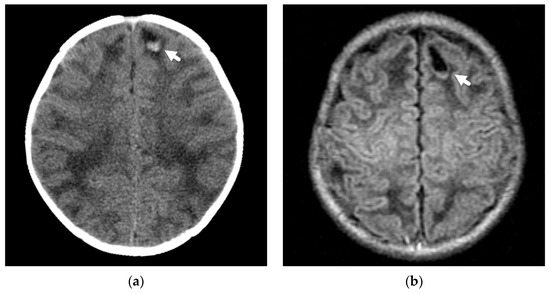

Axonal injuries may be very subtle on CT imaging but may appear as multiple, punctate, low-attenuation foci or petechial hemorrhages, usually involving hemispheric white matter, the corpus callosum, cerebellum, and brainstem. Deep subarachnoid hemorrhage and brain swelling may be seen as associated findings on both CT and MRI. Susceptibility-weighted imaging is a key MR sequence for detecting the punctate hemorrhagic foci, and diffusion-weighted imaging aids in the detection of non-hemorrhagic, traumatic axonal injury Figure 4.

Figure 4.

Axonal injury and lacerations/contusional tears in a 4-month-old male presenting with seizure and lethargy. (a) Initial axial CT image demonstrates right parafalcine high-attenuation subdural hemorrhage (white arrow); (b) coronal reconstruction in bone algorithm demonstrates a right parietal bone fracture (black arrow) with overlying soft tissue swelling (white arrowhead); (c) axial T2-weighted MR image on day 4 demonstrates bilateral lacerations/contusional tears with fluid-hemorrhagic levels near the temporal-occipital lobe junctions (white arrows); (d) axial susceptibility-weighted image demonstrates layering hemorrhage in lacerations/contusional tears (white arrows) and axonal injury near the cortical-white matter junction in each frontal lobe (black arrows).